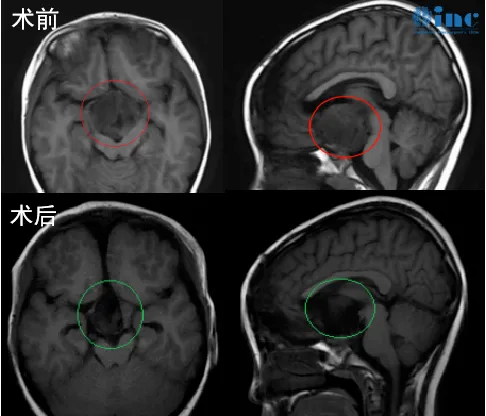

患者情况:2018年7月,年仅5岁的小冬患巨大视神经胶质瘤,肿瘤严重压迫视神经等重要功能神经和脑组织,眼睛几乎没有光感,父母为他访遍国内神经外科医院,均表示这个位置无法手术,或者手术风险很大但是切除率很低,不建议治疗。看着孩子病情一天天恶化,家长心急如焚,经过多方查询才找到INC,并在INC协助下联系到巴特朗菲教授。巴教授详细诊断小冬病情后表示,尽管视神经被肿瘤浸润包裹,但还是有很大机会切除肿瘤,且手术不会导致失明等症状。

治疗过程:巴教授根据肿瘤具体位置、大小和形态制定个体化手术方案,通过额骨颅骨开颅术和大脑半球间穹窿入路,在神经电生理监测护航下实现近全切肿瘤,术中无新发功能神经损伤,术后无新发并发症。术后两周出院,小冬视力明显好转,可自行站立、短距离行走。术后3年半的他,可以看见妈妈,笑容温暖如初、开朗如常。